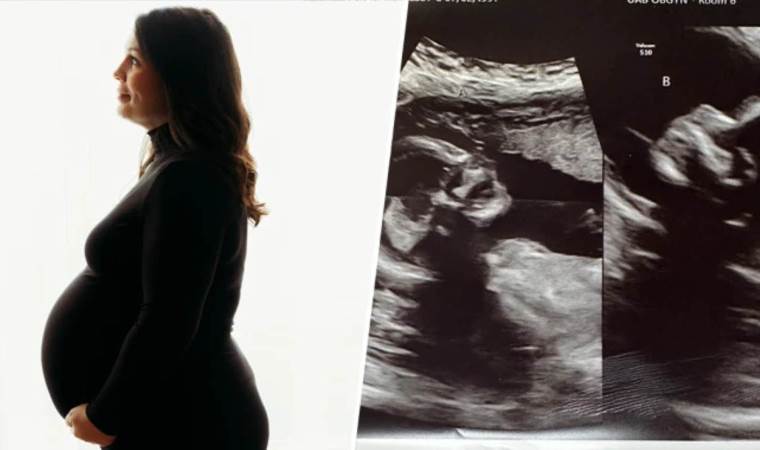

ABD'li üç çocuk annesi 32 yaşındaki Kelsey Hatcher, "uterus didelphys" ya da iki rahim adı verilen nadir bir rahim anomalisi ile doğdu ve hamilelik testinin pozitif çıkmasının ardından şaşırtıcı bir biçimde, her iki rahimde de hamile olduğu ortaya çıktı.

Hatcher, doktorlara göre "şaşırtıcı" ve nadir bir şekilde, her iki rahminde de birer kız bebek dünyaya getirmeyi bekliyor.